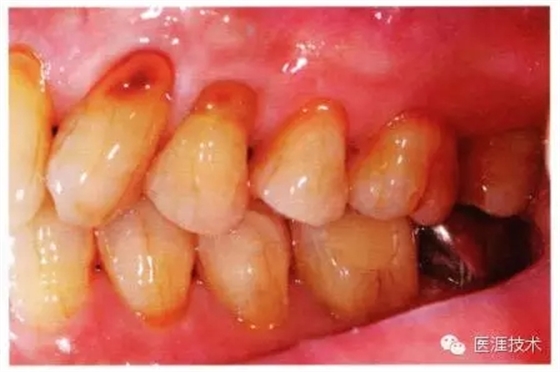

55歲牙周炎男性的臨床照片

55歲男性抽煙患者(1天20支、抽煙35年)。菌斑控制得不好。通過牙周探診,全頜有4~9mm的牙周袋,有1~3度的根分叉部病變。通過X光片觀察,上頜前牙中度牙槽骨吸收,其他地方有中度牙槽骨吸收。受吸煙影響,牙齦纖維性肥厚,呈紅黑色。牙齦幾乎沒有浮腫和發(fā)紅,所以這個病例是從外觀上無法預(yù)測病癥嚴(yán)重程度的病例。